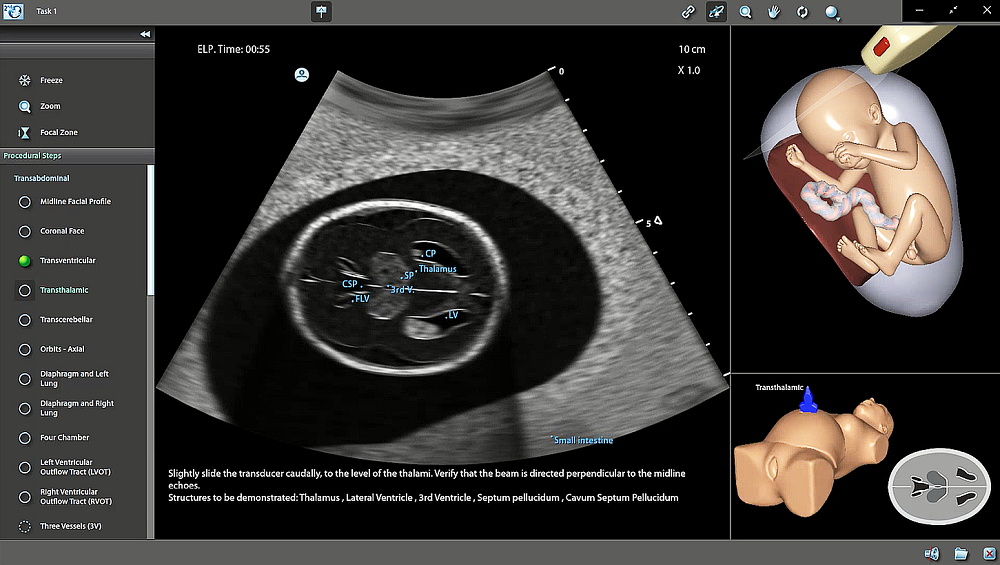

Bessere Früherkennung angeborener Herzfehler dank Künstlicher Intelligenz und Simulatortraining7. November 2022 Johannes Steinhard betreut Fortbildungsmaßnahmen am High-End-Simulatorsystem. Foto: ©HDZ NRW Wie Fehlbildungen beim Ungeborenen zukünftig noch besser als bisher erkannt werden können, zeigt eine neue Studie über Künstliche Intelligenz und Simulation. Der in Münster und Bad Oeynhausen tätige Pränatalmediziner und Gynäkologe Dr. Johannes Steinhard leitet eine Arbeitsgruppe, die sich seit Jahren mit Simulationstraining und Künstlicher Intelligenz in der Pränatalmedizin beschäftigt. Er wurde nun für einen der auf dieser Arbeit beruhenden besten wissenschaftlichen Vorträge jüngst auf der 64. Jahrestagung der Deutschen Fachgesellschaft für Gynäkologie und Geburtshilfe (DGGG) in München ausgezeichnet. Die Mutterschaftsrichtlinien zur allgemeinen Schwangerschaftsvorsorge sehen drei Ultraschalluntersuchungen vor, die in aller Regel in der zehnten, 20. und 30. Schwangerschaftswoche durchgeführt werden. In der Qualität der Screenings hinkt Deutschland im Vergleich zu seinen Nachbarländern allerdings nachweislich hinterher. „Das zeigt sich besonders bei der Früherkennung angeborener Herzfehlbildungen“, sagt Steinhard, Leiter der Abteilung für Fetale Kardiologie am Herz- und Diabeteszentrum NRW (HDZ NRW), Bad Oeynhausen, und jüngst ausgezeichneter DGGG-Preisträger. „Durchschnittlich werden nur etwa 43 Prozent der schweren, für das Kind direkt nach der Geburt gefährlichen Herzfehler erkannt.“ Das kann sich durchaus dramatisch auf die Entwicklung und weitere Behandlungen des Kindes auswirken. Was ist also zu tun, um Qualifikation, Wissen und Erfahrung der Ärzte angesichts hoher Ausbildungskosten und schwieriger Personalsituation zu verbessern? „Es müssen dringend neue Konzepte gefunden werden, die den Untersuchenden bei der vorgeburtlichen Ultraschalldiagnostik helfen“, sagt Steinhard, der sich seit Jahren am Zentrum für Pränatale Medizin Münster und der Bad Oeynhausener Universitätsklinik (Ruhr-Universität Bochum) für die Ausbildung des medizinischen Nachwuchses engagiert. Der Mediziner und Wissenschaftler hat sich dabei besonders dem Einsatz intelligenter Systeme sowie dem Simulatortraining gewidmet und die damit verbundenen Lerneffekte untersucht. Ultraschall-Experten nach sechs Wochen Training 22 Studentinnen und Studenten ohne Ultraschallerfahrung wurden zur Hälfte für die Feindiagnostik der fetalen Organe und in der erweiterten fetalen Herzuntersuchung nach dem anspruchsvollen Standard der American Heart Association an einem High-End Simulator ausgebildet. Die Besonderheit dieses Simulators ist ein sehr realistischer, virtueller Fetus, der sich auch per Zufallsgenerator bewegen kann. Nach einer kurzen Einführung haben sie selbständig sechs Wochen lang jeweils zwei Stunden pro Woche trainiert. Sowohl die Studierenden als auch zehn Ärzte eines großen Perinatalzentrums sowie zehn über die Deutsche Gesellschaft für Ultraschall in der Medizin (DEGUM) zertifizierte Experten wurden bezüglich der Schnelligkeit und Genauigkeit der Einstellung der definierten Standardebenen getestet. Insgesamt sind auf diese Weise über 80 Stunden Tests ausgewertet worden. Trainingsmodus: Die Vermessung des Herzens mittels Ultraschall kann mit dem Simulator geübt werden. Bild: ©HDZ-NRW Die Ergebnisse sind auch für Steinhard beeindruckend: „Medizinstudierende ohne Vorerfahrung konnten im Rahmen eines strukturierten sechswöchigen Trainings ihre Diagnosesicherheit bei der Durchführung einer fetalen Echokardiographie eindrucksvoll verbessern. Die Ergebnisse sind vergleichbar mit denen der Experten, die über einen Erfahrungsschatz von mehr als 260.000 Ultraschalluntersuchungen verfügen.“Nicht nur für das Zeit- und Kostenmanagement im Rahmen der ärztlichen Qualifikation und Weiterbildung, sondern vor allem für die medizinische Qualität und Sicherheit für die Allerkleinsten im klinischen und im Praxisalltag zeigen die erhobenen Daten offenkundig, „dass wir von intelligenter, workflowbasierter Technik ungemein profitieren können“, so Steinhard. „Und nicht nur in der Pränatalmedizin zählen cloudbasierte, weltweite Lernplattformen und dadurch stetig präzisere Simulatortechniken und künstliche Intelligenz zu den vielversprechendsten Entwicklungen der letzten Jahre.“